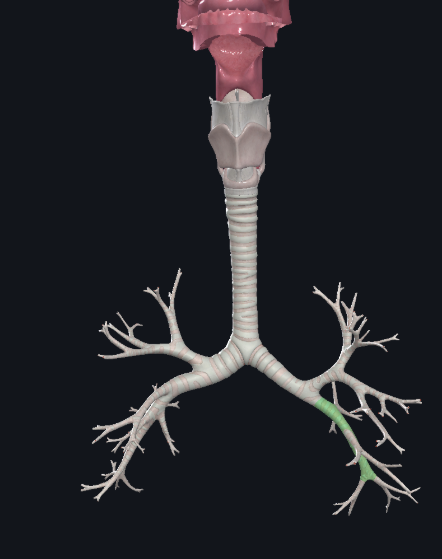

What structure is this?

Right inferior lobar bronchus

What structure is this?

Left main bronchus

What structure is this?

Left superior lobar bronchus

What structure is this?

Left inferior lobar bronchus